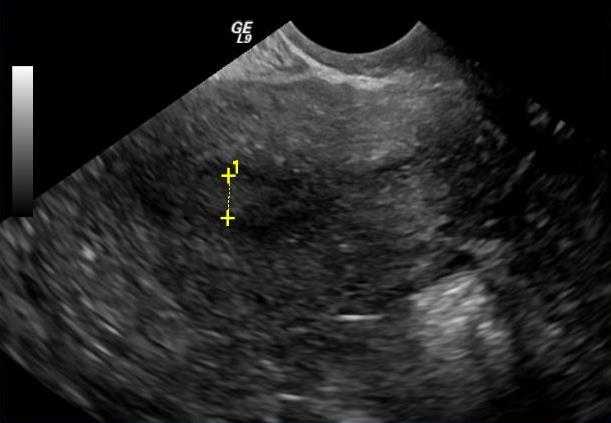

Косвенные признаки определяются на ультразвуковом обследовании. Только опытный врач сможет отличить симптомы начальной и хронической формы болезни. Эхо-признак эндометрита матки можно определить по следующим факторам:

- степень увеличения маточной полости,

- толщина образования,

- наличие и количество спаек.

Когда признаки эндометрита на ультразвуковом обследовании не дают развернутой клинической картины о тяжести и форме развития, то у женщины нужно взять материал для биопсии.

Эффективный метод диагностики эндометрита это ультразвуковое обследование матки. Врач оценивает толщину слизистой оболочки, наличие гнойных образований, сгустки крови, остатки плацентарной ткани, воспаление, а также изменения эхогенных слизистых оболочек.